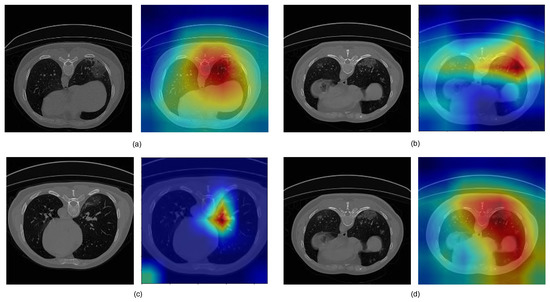

3.3. Analysis of the Performance of the Proposed Model